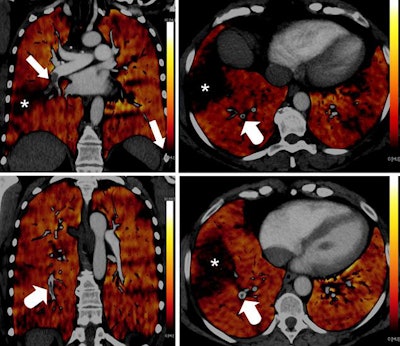

Emphysema causes a true decrease in pulmonary circulation due to lung parenchyma destruction. This is visualized in PBV images as a perfusion defect, but it should not be mistaken for hypoperfusion due to embolism (see figure below).

Coronal images (top and bottom left) of a 49-year-old woman with alpha-1 antitrypsin deficiency show advanced lower lobe emphysema with correlating PBV defects. Motion artifacts due to cardiac or respiratory motion typically cause PBV pseudodefects adjacent to the heart or hemidiaphragm. Axial PBV images show PBV pseudodefects due to cardiac motion (top right) and diaphragm motion (bottom right) (arrows).An algorithm allocates a ratio of air and soft tissue within a voxel, determining lung parenchyma containing air, and iodine content is quantified and visualized in color-coded perfusion maps.